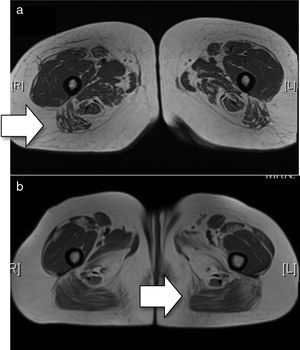

Clinical CaseA female aged 30 was diagnosed with NAM as a result of the presence of proximal myopathy, dysphagia to liquids and dysphonia of 2-month onset, elevation of muscular enzymes (CK 5.922UI/l, aldolase 84UI/l), electromyography with myopathic pattern, signs of intramuscular oedema on the magnetic resonance in shoulder and pelvic girdles (Fig. 1a) and anatomical–pathological findings of necrotic myopathy which had defied standard treatment (corticoids, inmunoglobulins, azathioprine).

(a) Baseline MRI (T1 sequence). There is minimal oedema in the distal end of both the sartorius and gracilis muscles. Compromise of both compartments, with the lateral mass more affected in the anterior compartment and the middle masses more affected in the posterior compartment. In general, there is greater posterior compromise (arrow). (b) MRI after treatment with rituximab (T1 sequence). Bilateral and symmetrical compromise is noted of both compartments with muscular atrophy observed with diffuse fatty deposits. The lateral and middle masses are more affected in the anterior compartment and the hamstring muscles are more affected in the posterior compartment, with predominance of compromise in the posterior compartment (arrow).

Magnetic resonance of the muscles after 2 years showed an absence of any signs of inflammatory activity (Fig. 1b).

In our case, two cycles of rituximab were administered, leading to an exacerbation on reduction of the dose of methotexate, with favourable subsequent control when the dose was increased. The CK values of the patient were lower than that published in other series and this may be one of the reasons why a good therapeutic outcome was achieved. The imaging findings were also of note, where greater compromise of the posterior thigh compartment was noted when there were no apparent clinical signs of this.